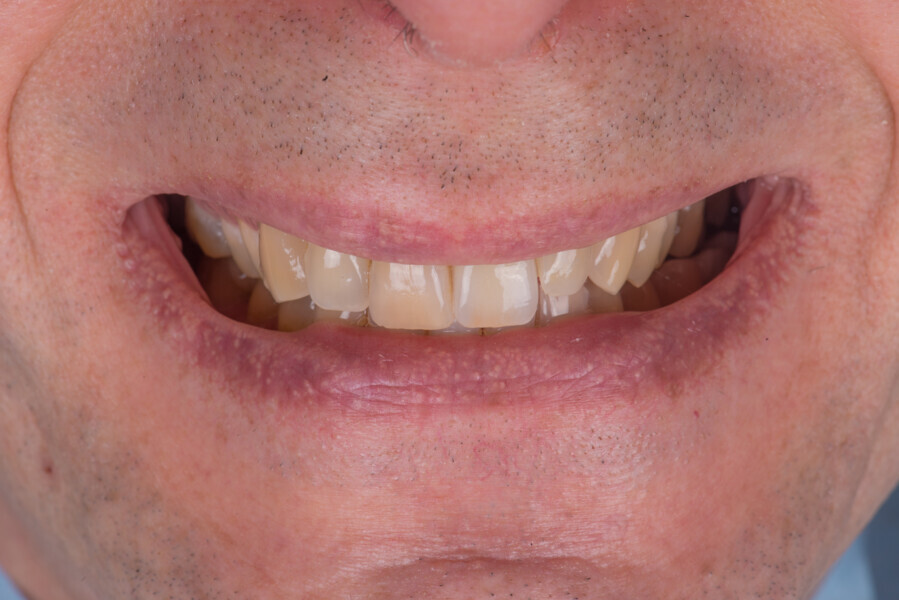

Immediate placement and restoration of a Straumann BLX implant replacing maxillary incisors